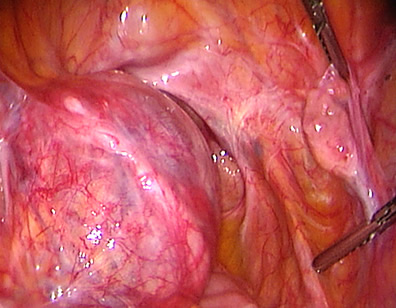

This lady had an ectopic pregnancy in the left tube. See the dilated area in the tube.